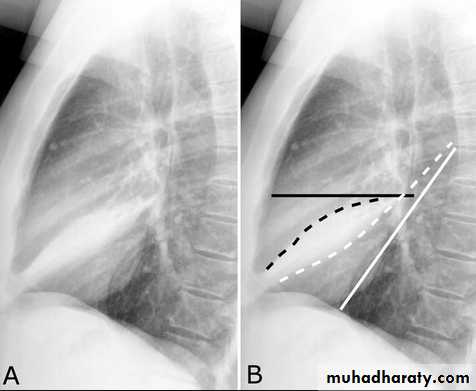

Subpulmonary pleural effusion. On the (A) erect PA and (B) lateral radiograph the effusion simulates a high hemidiaphragm. (C) Ultrasound and (D) CT clearly show that the effusion is located above the diaphragm. Arrows = diaphragmatic area.